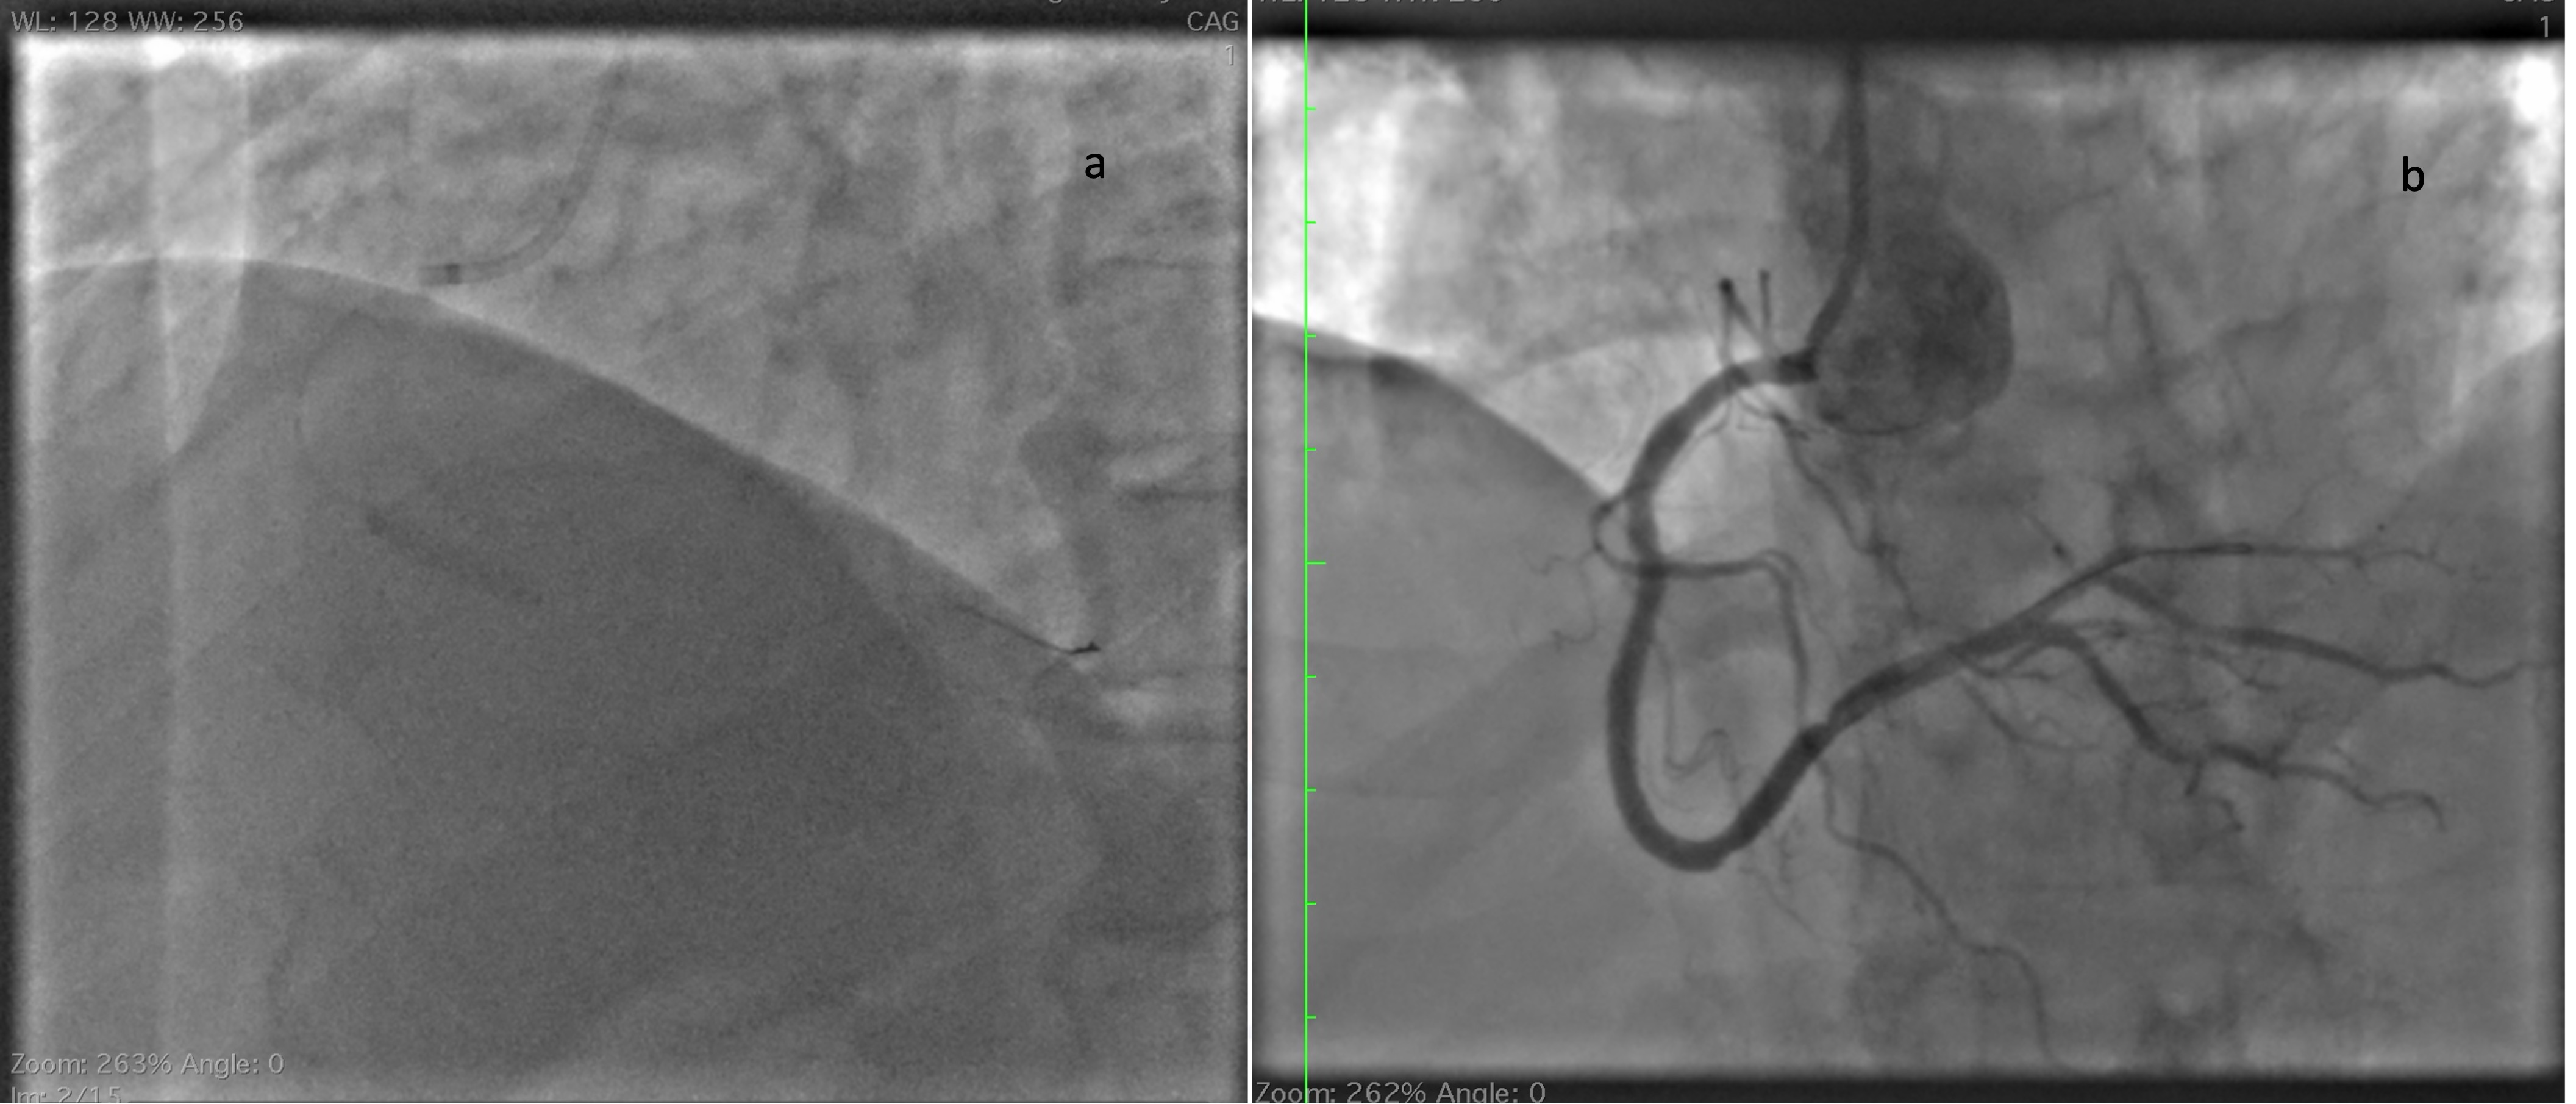

He was immediately shifted to catheterization laboratory and angiogram showed mild plaque in left anterior descending artery (Figure 2)(Video 1) and significant stenosis In distal right coronary artery with additional mild plaque proximally (Figure 3) (video 2).